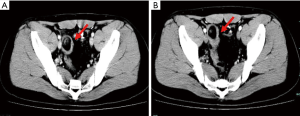

Case 2 was a 17-year-old boy who presented with intermittent dull abdominal pain and melena for 1 month, and was admitted to hospital for further evaluation. Physical examination revealed an abdominal mass in the right lower quadrant; however, there were no signs of peritonitis. Blood tests showed a low hemoglobin level of 75 g/L, while gastroscopy, capsule endoscopy, and colonoscopy were unremarkable. Abdominal and pelvic CT showed bowel obstruction and intussusception with a 5 cm × 2 cm mass (Figure 2). Partial ileal resection of the intussusception was performed, followed by a side-to-side anastomosis. Histopathological analysis of the specimen revealed a benign ileum with HP, with no evidence of malignancy. He had no further abdominal pain or melena after surgery.